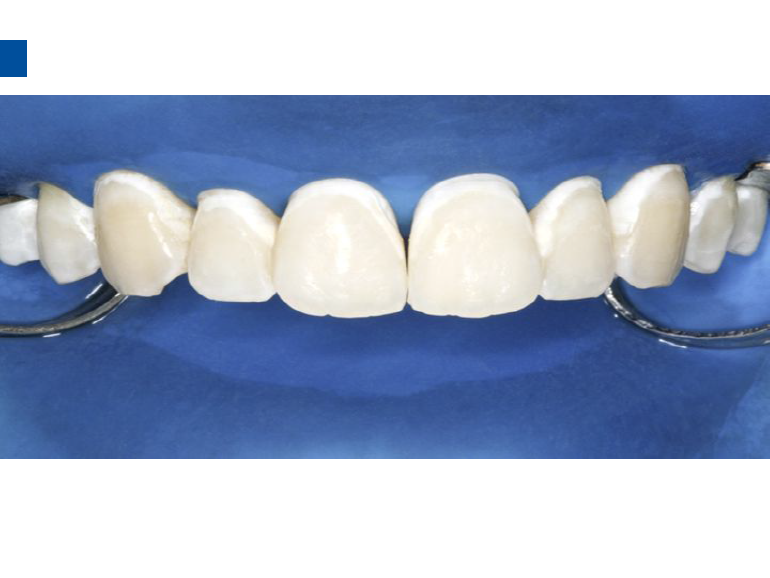

微创牙科治疗是一种全新的龋病治疗理念,着眼于疾病的早发现、早诊断、早治疗。树脂渗透治疗是介于再矿化治疗和充填治疗之间的一种创新的治疗手段,通过微量的去除牙体组织,达到加固脱矿釉质、阻止进一步脱矿的目的。

lcon渗透基于封闭釉质龋空隙的一种特殊树脂的渗透,封闭釉质龋小孔,从而阻断致龋酸传播途径,阻止龋病进一步发展。这种材料操作方法简单,对牙体组织损伤轻微,不用通过麻醉和磨切牙体来达到加固脱矿釉质,同时可以改变釉质龋表面的白色或棕色改变,达到美观修复效果,是对龋病微创治疗的突破。